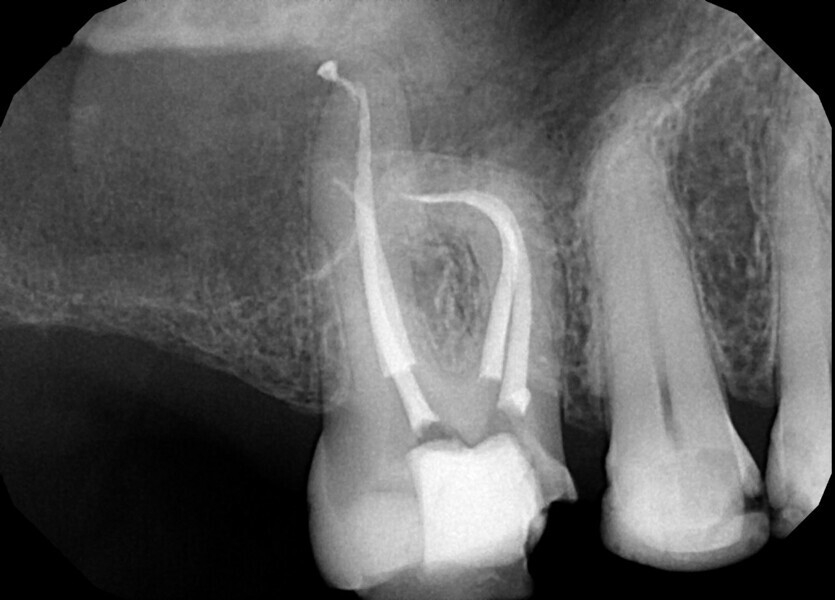

Fig. 3: Calcium hydroxide extruded into the mandibular canal through a perforation.